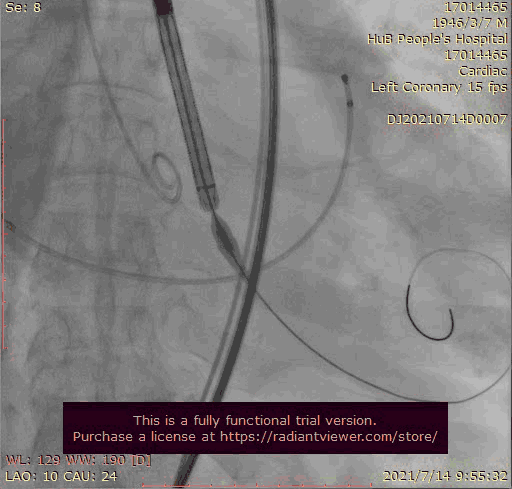

输送器跨瓣

大结构瓣膜稳定性差,输送器使瓣膜跳到瓣上

奇思妙想使用射频消融大头压住支架至窦底